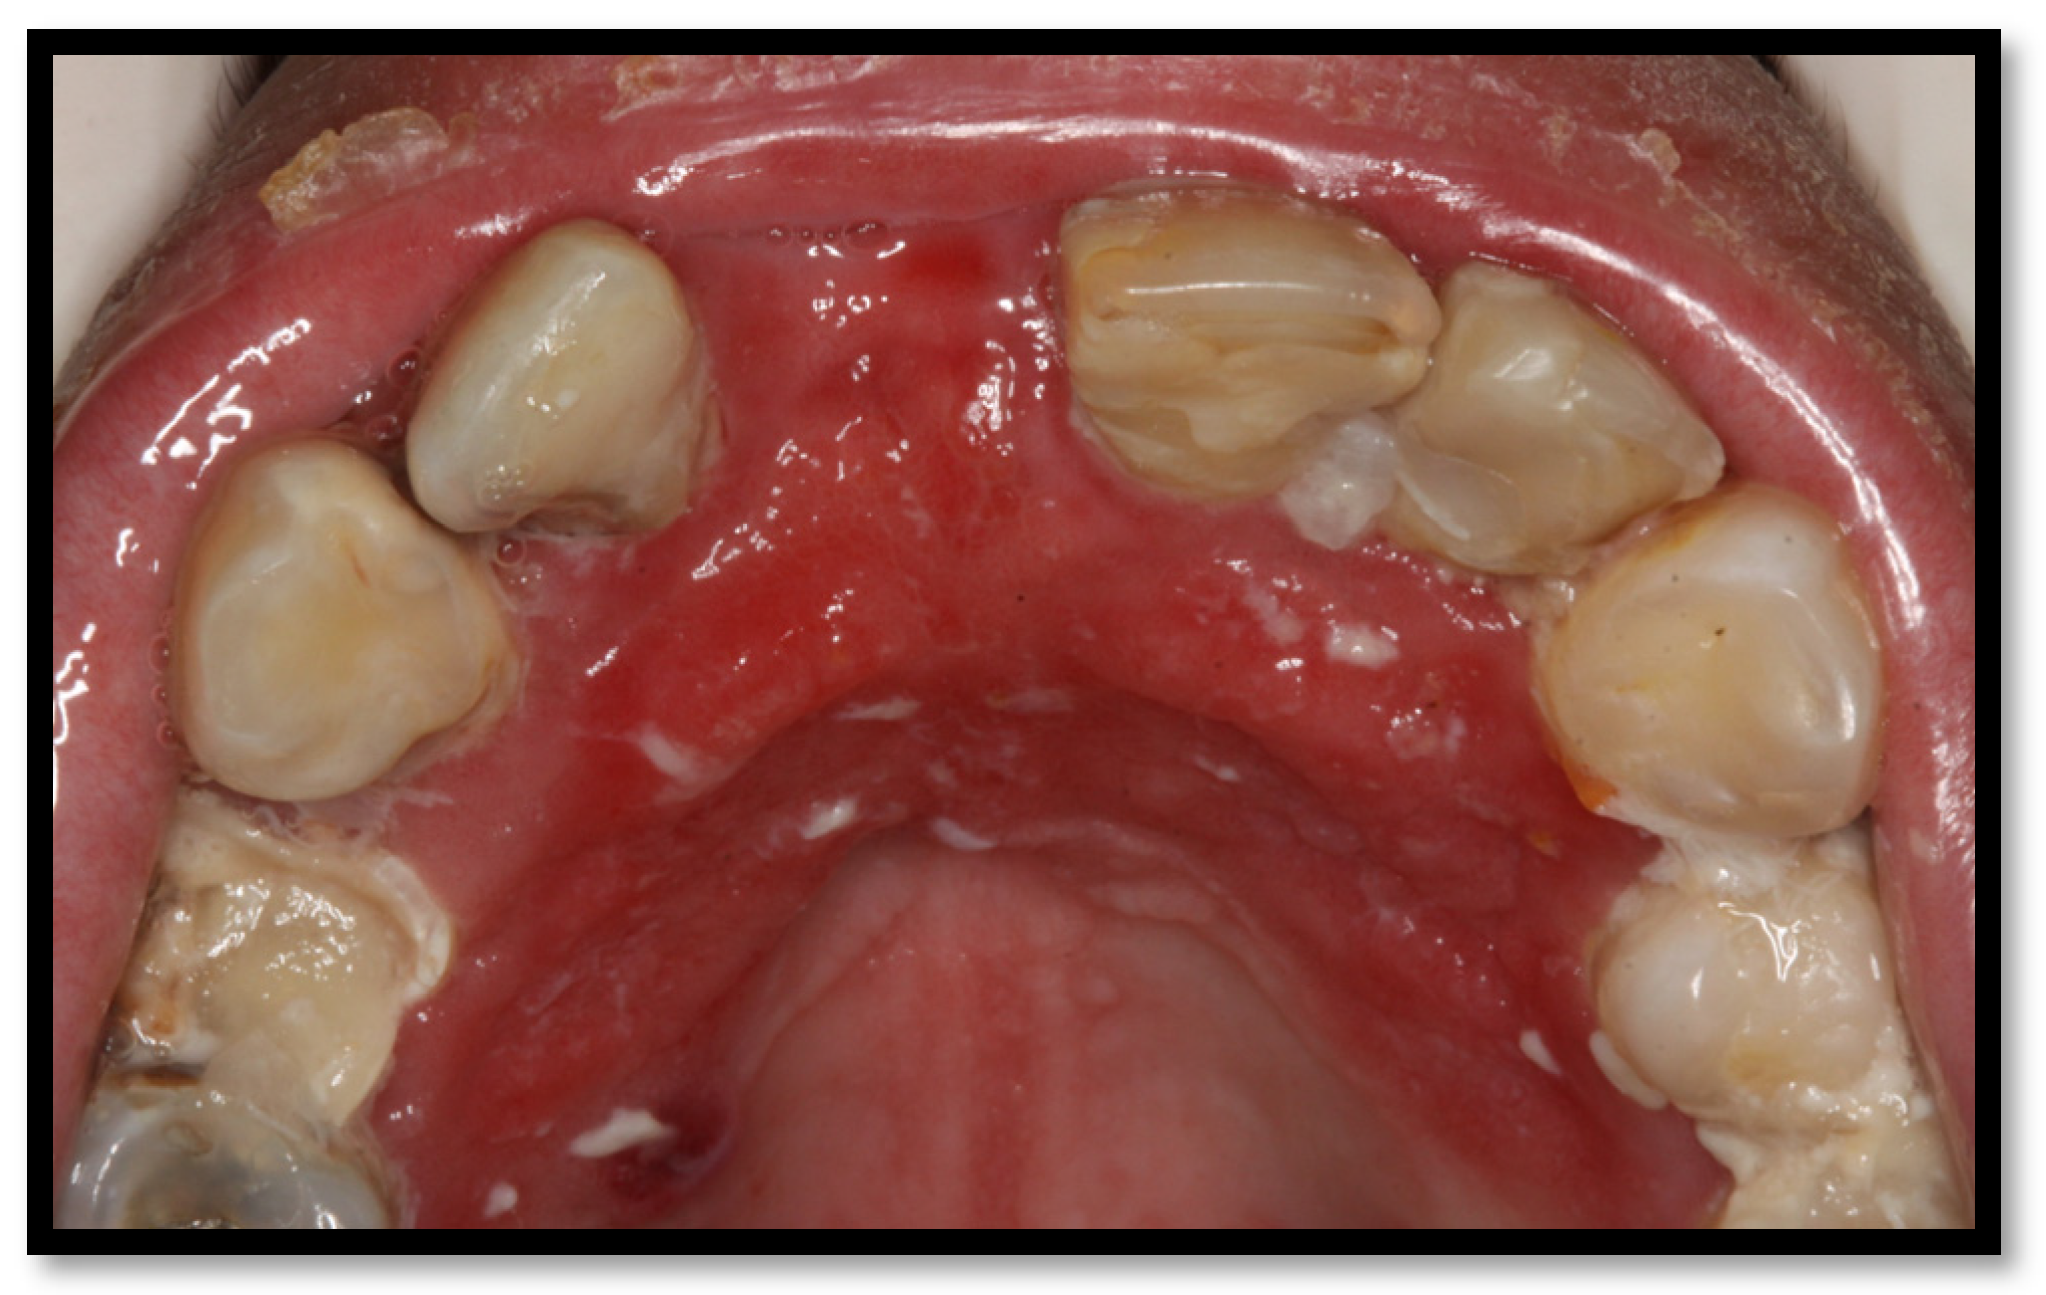

3. Periodontal Disease

3.1. Linear Gingival Erythema

3.2. Periodontitis

3.3. Necrotizing Gingivitis (NG)

3.4. Necrotizing Periodontitis (NP)